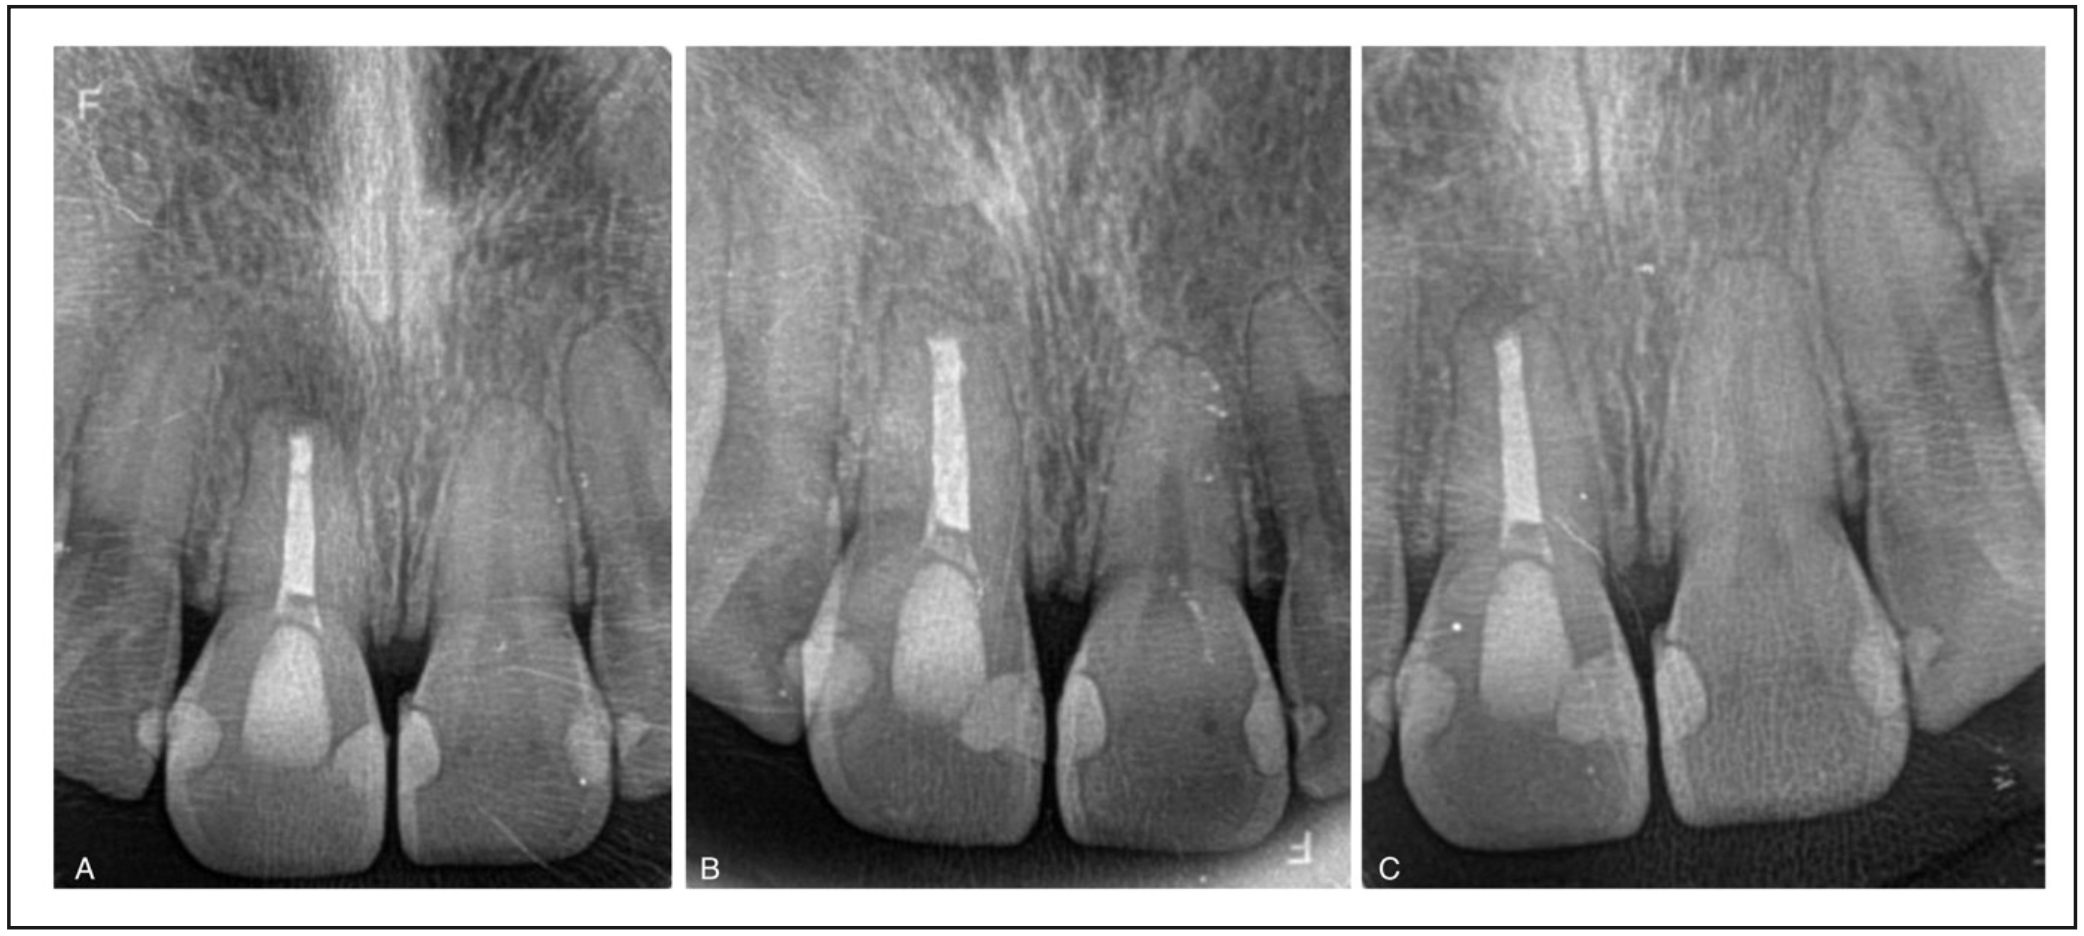

En el examen radiológico se observa una lesión osteolítica apical circunscrita de tamaño 5x8 mm. (Figura 1); además, se decidió complementar con tomografía computarizada de haz cónico debido a la movilidad presentada (Figura 2) en la que se logró visualizar la lesión en forma más precisa entregando una medida de aproximadamente 5x8,5x5mm, con compromiso de la tabla ósea vestibular, manteniendo una banda de tejido óseo a nivel cervical vestibular de entre 3,51 a 4,36 mm y mantención de la tabla palatina.

Figura 1. Radiografía retroalveolar de diagnóstico del diente

1.1. Canal radicular amplio, con remodelado. Se observa lesión osteolítica apical extensa circunscrita.